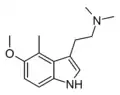

Substituted tryptamines, or serotonin analogues, are organic compounds which may be thought of as being derived from tryptamine itself. The molecular structures of all tryptamines contain an indole ring, joined to an amino (NH2) group via an ethyl (−CH2–CH2−) sidechain. In substituted tryptamines, the indole ring, sidechain, and/or amino group are modified by substituting another group for one of the hydrogen (H) atoms.

| 4-Methyl-DMT | artificial | 4-CH3 | CH3 | CH3 | 4,N,N-trimethyltryptamine | 28289-23-8 |